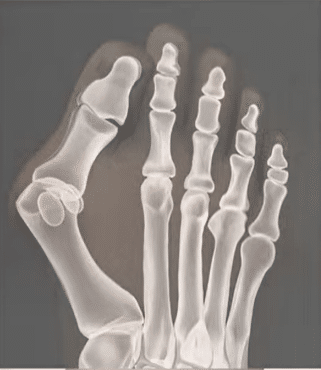

butyok mutet elott